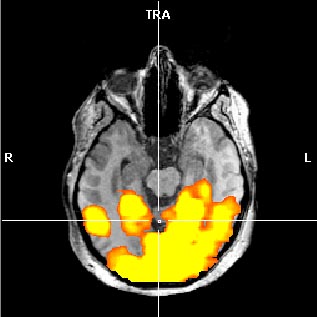

Lo resultados que hemos obtenido en pacientes con ELT concuerdan con la literatura previa, ya que existe una organización atípica de la memoria en este tipo de pacientes donde se obtienen activaciones con una distribución preferentemente contralesional (ver Figuras 2A y 2B).

Activación cerebral de predominio izquierdo durante la tarea de codificación de imágenes (2A) y “paseo por tu ciudad” (2B) en un paciente con ELT derecho.

| 2A.- Codificación de imágenes |

2B.- “Paseo por tu ciudad” |